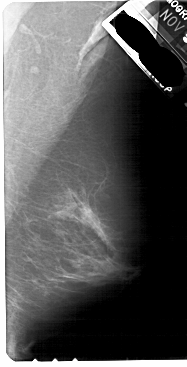

A_1840_1.RIGHT_MLO

RIGHT_CC LINES 5431 PIXELS_PER_LINE 2431 BITS_PER_PIXEL 12 RESOLUTION 43.5 NON_OVERLAY

RIGHT_MLO LINES 5491 PIXELS_PER_LINE 2791 BITS_PER_PIXEL 12 RESOLUTION 43.5 NON_OVERLAY